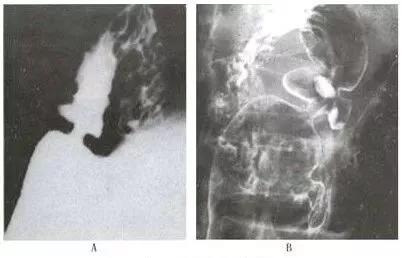

十二指肠球部溃疡X线影像

A 充盈相示:大弯侧腔外龛影;B 双对比相示:前后壁两个溃疡相吻